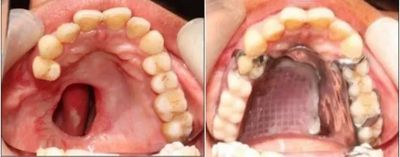

Obturators play a critical role in the rehabilitation of maxillectomy patients. A maxillectomy is a surgical procedure that removes part or all of the maxilla, or upper jaw bone, typically due to a malignant tumor. This surgery often results in a communication between the oral and nasal cavities, causing functional issues such as difficulty speaking, eating, and swallowing, as well as esthetic concerns.

An obturator is a maxillofacial prosthetic device that closes this communication, restoring function and appearance. Here's how obturators can help maxillectomy patients:

Obturators can be temporary or definitive. Temporary obturators are often used immediately after surgery to aid in healing, while definitive obturators are custom-made to provide the best fit, function, and esthetics for the long term. Despite their benefits, it's worth noting that obturators are a prosthetic solution and will require ongoing care and regular adjustments over time. Consult with your Maxillofacial Rehab Specialist today!!